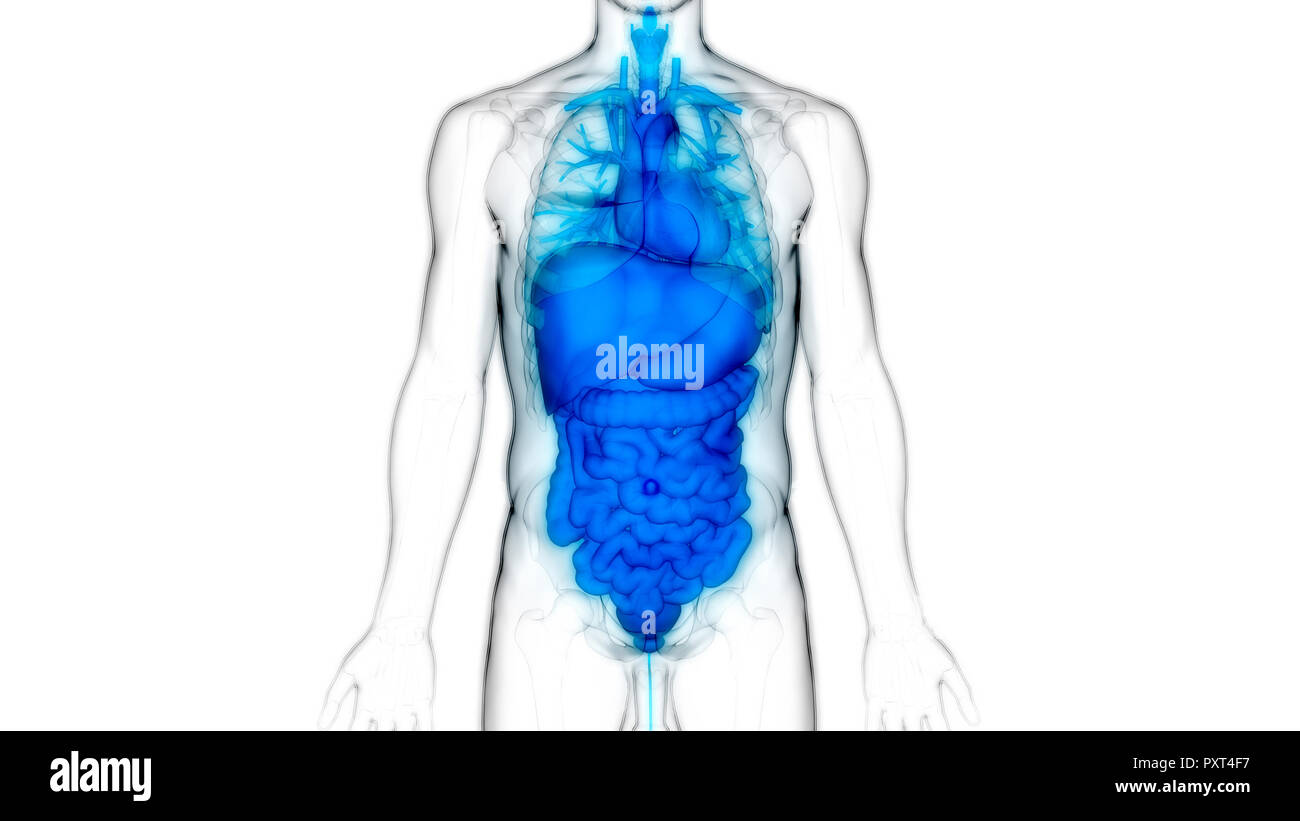

Human Complete Internal Organs Anatomy Stock Photohttps://www.alamy.com/image-license-details/?v=1https://www.alamy.com/human-complete-internal-organs-anatomy-image354474317.html

Human Complete Internal Organs Anatomy Stock Photohttps://www.alamy.com/image-license-details/?v=1https://www.alamy.com/human-complete-internal-organs-anatomy-image354474317.htmlRF2BGKKH1–Human Complete Internal Organs Anatomy

Human Complete Internal Organs Anatomy Stock Photohttps://www.alamy.com/image-license-details/?v=1https://www.alamy.com/human-complete-internal-organs-anatomy-image330947658.html

Human Complete Internal Organs Anatomy Stock Photohttps://www.alamy.com/image-license-details/?v=1https://www.alamy.com/human-complete-internal-organs-anatomy-image330947658.htmlRF2A6BY36–Human Complete Internal Organs Anatomy

Human Body Organs Anatomy Stock Photohttps://www.alamy.com/image-license-details/?v=1https://www.alamy.com/human-body-organs-anatomy-image223035828.html

Human Body Organs Anatomy Stock Photohttps://www.alamy.com/image-license-details/?v=1https://www.alamy.com/human-body-organs-anatomy-image223035828.htmlRFPXT4D8–Human Body Organs Anatomy

Human Body Organs Anatomy Stock Photohttps://www.alamy.com/image-license-details/?v=1https://www.alamy.com/human-body-organs-anatomy-image223035883.html

Human Body Organs Anatomy Stock Photohttps://www.alamy.com/image-license-details/?v=1https://www.alamy.com/human-body-organs-anatomy-image223035883.htmlRFPXT4F7–Human Body Organs Anatomy